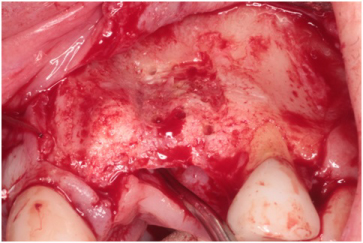

The patient received 2 gm of amoxicillin as an antibiotic prophylaxis (Zimox, Pfizer Inc., USA). Intravenous sedation was administered and approximately 30 cc of venous blood was drawn in order to prepare 3-5 cc of platelet rich fibrin (PRF). 2% Lidocaine HCL 1:100, 000 with epinephrine (Septodont Cook-Waite, Lancaster, PA, USA) was used for local infiltration at the #s 6-11 sites. Both surgical sites were prepared in the same manner. Bilateral papilla sparing incisions were completed (Figure 4 and Figure 5). Once the labial or buccal aspects were exposed, a #7011 bur was used to perforate the bone and establish bleeding bone (Figure 6 and Figure 7). At both sites, a Cytoplast® Ti-250 (Osteogenics Biomedical, Lubbock, TX, USA) titanium reinforced membrane shaped and sized to cover the proposed GBR sites and allow space for the bone regeneration to occur. The membrane each were secured with bone tacks first at the vestibule (Tru Tack® ACE Boston, MA, USA) (Figure 8). Then MinerOss® bone graft (Biohorizons, Birmingham, AL, USA) was placed at both surgical sites (Figures 9 and Figure 10) followed by a single superior membrane bone tack (Figures 11 and Figure 12). PRF was placed over the membranes (Figures 13 and Figure 14) and the surgical flaps were repositioned without tension with Cytoplast® and chromic sutures (Figures 15 and Figure 16).

Figure 6: Bleeding bone established at the #7 site with a #701 bur. View Figure 6

Figure 7: Site #s 9 and 10 bleeding bone established with a #701 bur. View Figure 7